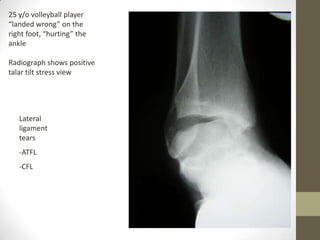

25 y/o volleyball player

“landed wrong” on the

right foot, “hurting” the

ankle

Radiograph shows positive

talar tilt stress view

Lateral

ligament

tears

-ATFL

-CFL